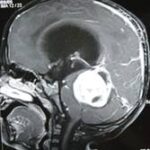

It is usually diagnosed by an increasing head circumference in infants, an ultrasound scan, a CT scan or sometimes an MRI scan.

હાઈડ્રોકેફલસ સૌથી સામાન્ય કારણ છે. અને તેનું સચોટ નિદાન નાના બાળકોમાં સોનોગ્રાફી દ્વારા અને મોટા બાળકોમાં સી.ટી.સ્કેન અથવા એમ.આર.આઈ.થી થઈ શકે છે.

हाइड्रोसीफेलस एक सर्वसामान्य कारण है। बच्चों के मामले में इसका सटीक निदान सोनोग्राफी के द्वारा तथा वयस्कों में सी.टी. स्कैन अथवा एम.आर.आई के द्वारा किया जाता है।